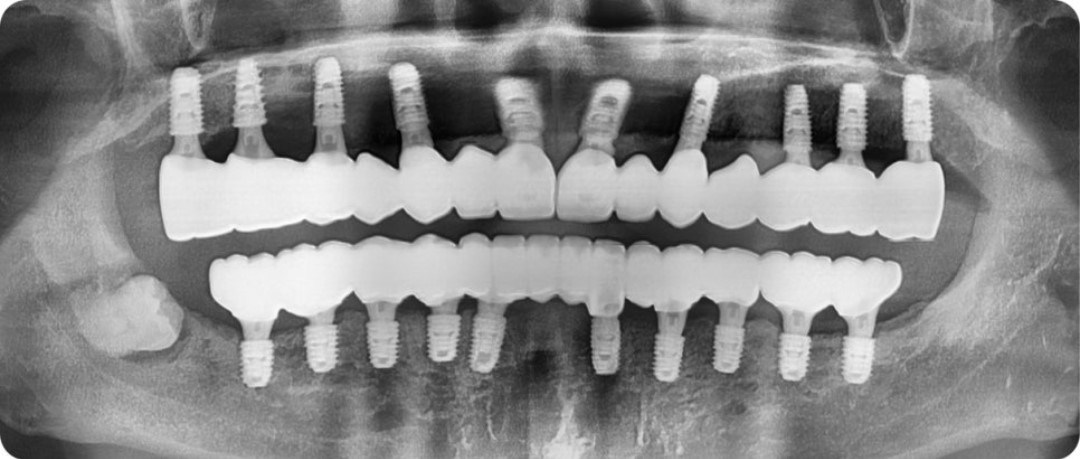

파노라마 사진에서 보이다시피 위, 아래 어금니는 오래전에 상실한 상태였고

남아있는 앞니마저 흔들리고 잇몸뼈도 많이 녹아,

앞으로 1년도 채 안돼서 빠질 가능성이 높아 보였습니다.

김태수님은 위 10개, 아래 10개의 임플란트를 식립하고

뼈이식을 동반한 전체 임플란트 치료를 받으셨는데요.

이전부터 앓고 계시던 만성 치주염으로 이미 잇몸뼈가 많이 소실된 상태인데다가,

틀니를 5년 정도 사용하셔서 잇몸뼈의 폭과 높이가

임플란트를 심기에 뼈가 많이 부족한 상태였습니다.